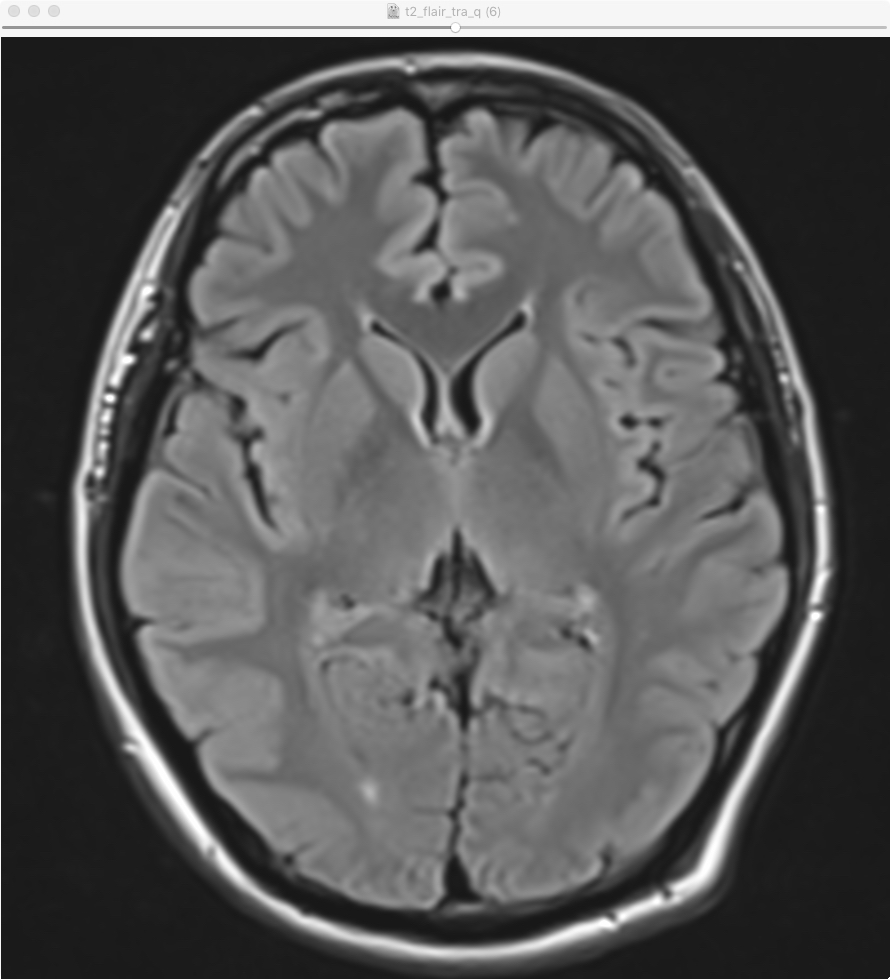

画像サンプル |

---|